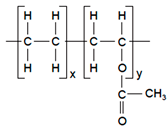

| Polymers | Structure | Fabrication Method | Commercial Products/Literatures | Comments | Reference |

|---|---|---|---|---|---|

| Polycarbonate (PC) |  | Ion-track etching | Estrogen | Excellent stability against oxidation and biodegradation and improves antifouling properties | [151] |

| Polyethylene (PE) |  | Ion-track etching | Catapress (Clonidine), Boehringer IngelheimClimara (Estradiol), Berlex | Physico-chemical stability andordered pore formation with superior membrane performance | [152] |

| Polyethylene terephthalate (PET) |  | Lithography | Ketoprofen | Biostable, antifouling, has better performance of membranes, in useful in preparing surgical meshes and ligaments | [153] |

| Polystyrene (PS) |  | Lithography | d-limonene, ibuprofen | Chemical resistance, easy processing, lower cost, exhibits enhancements in strength, stiffness, toughness, and ductility | [154] |

| PC, PE | - | Ion-track etching | Estraderm (Nitroglycerin), Rotta Research | Cost-effective and biocompatibility is fairly good | [155] |

| PC, PE, PET, PS | - | Phase separation | Deponit (Nitroglycerin), Pharma SchwarzHabitrol (Nicotine), Novartis | Cost-effective and biocompatibility is fairly good | [154,156] |

| Polyurethane (PU) |  | Sol-gel/solvent casting | Vivelle (Estradiol), Novartis | Good elasticity, biodegradable, suitable for hydrophilic drugs, biocompatibility is fairly good | [154] |

| Polysiloxane (silicone) |  | Sol-gel/solvent casting | Prostep (Nicotine), Lederle, Transderm Nitro (Nitroglycerin), AlzaSyncro-Mate-C (Norgestomet) | Better insulation, excellent biocompatibility, and fabricated easily for hydrophilic drugs | [157] |

| Polyisobutylene (PIB) |  | Solvent casting | Aminopyrene, Mitsubishi Petrochem Co., Japan | Good adhesive drug impermeable layer and high degree of tack or self-adhesion | [158] |

| Polymethyl methacrylate (PMMA), poly (2-hydroxy ethyl methacrylate) |  | Layer by layer deposition | Androderm (Testosterone), SmithKline Beecham | Physical strength and transparency | [159] |

| Polyvinyl alcohol (PVA), Poly (ethylene-co-vinyl acetate) |  | Solvent casting | Nitro-Dur I (Nitroglycerin), Key PharmaTestoderm TTS (Testosterone), Alza | Rate-controlling membranes, high membrane permeability, hydrophilicity and strength, suitable for lipophilic drugs | [160] |

| Polyacrylic acid, polyacrylate, polyacrylamide |  | Layer by layer deposition | Epinitril (Nitroglycerin), Rotta ResearchMonsanto (Fentanyl), Dow Corning | Good adhesivity and spreadability and contains a drug impermeable layer | [160] |

| Polylactides (PLA), polylactic-co-glycolic acid (PLGA), polyglycolides (PGA) |  , ,  | Sol-gel/solvent casting | Propranalol, Exxon Chemical Co. | Good biocompatibility; lactic and glycolic acids are the degradation products and they are easily eliminated from the body | [161,162] |

| Polyvinyl pyrrolidone (PVP), poly (N-vinyl pyrrolidone) |  | Sol-gel/solvent casting | Cytarabine, ara-ADA, Polyscience | Superior biocompatibility, has suspension capabilities, antinucleating agent, and enhances release rate | [163] |

| Polyethylene glycol (PEG) | Sol-gel/solvent casting | Miconozale, Rohm, Germany | Chemically inert and free of leachable impurities | [164] | |

| Oxide plus polymer | - | Sol-gel/solvent casting | Superior biocompatibility and has narrow pore size | ||

| Polymer coating on support membrane | - | Layer by layer deposition | [165] |